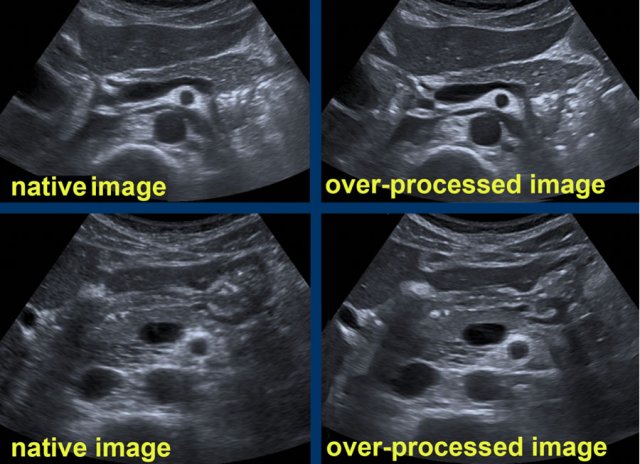

The processed US image: speckle-noise-reduction

• Advantages: sharper reflective contours, anechoic cysts and vessels, “smoothed image”

• Drawbacks:  creation of unrealistic boundaries and reflections, lower image resolution

• Use with great caution, as confusing artifacts may outweigh its advantages

Compare the native US images (left) of the pancreatic region with the strongly processed US images (right).

In these over-processed images the vessels have a sharper delineation with a completely anechoic lumen.

However, also unrealistic reflections and contours are “created”.

Note the unnatural bright reflections in the area dorsal from the pancreatic tail (right upper image) and note the bizarre contour of the stomach and the falciform ligament (right lower image).